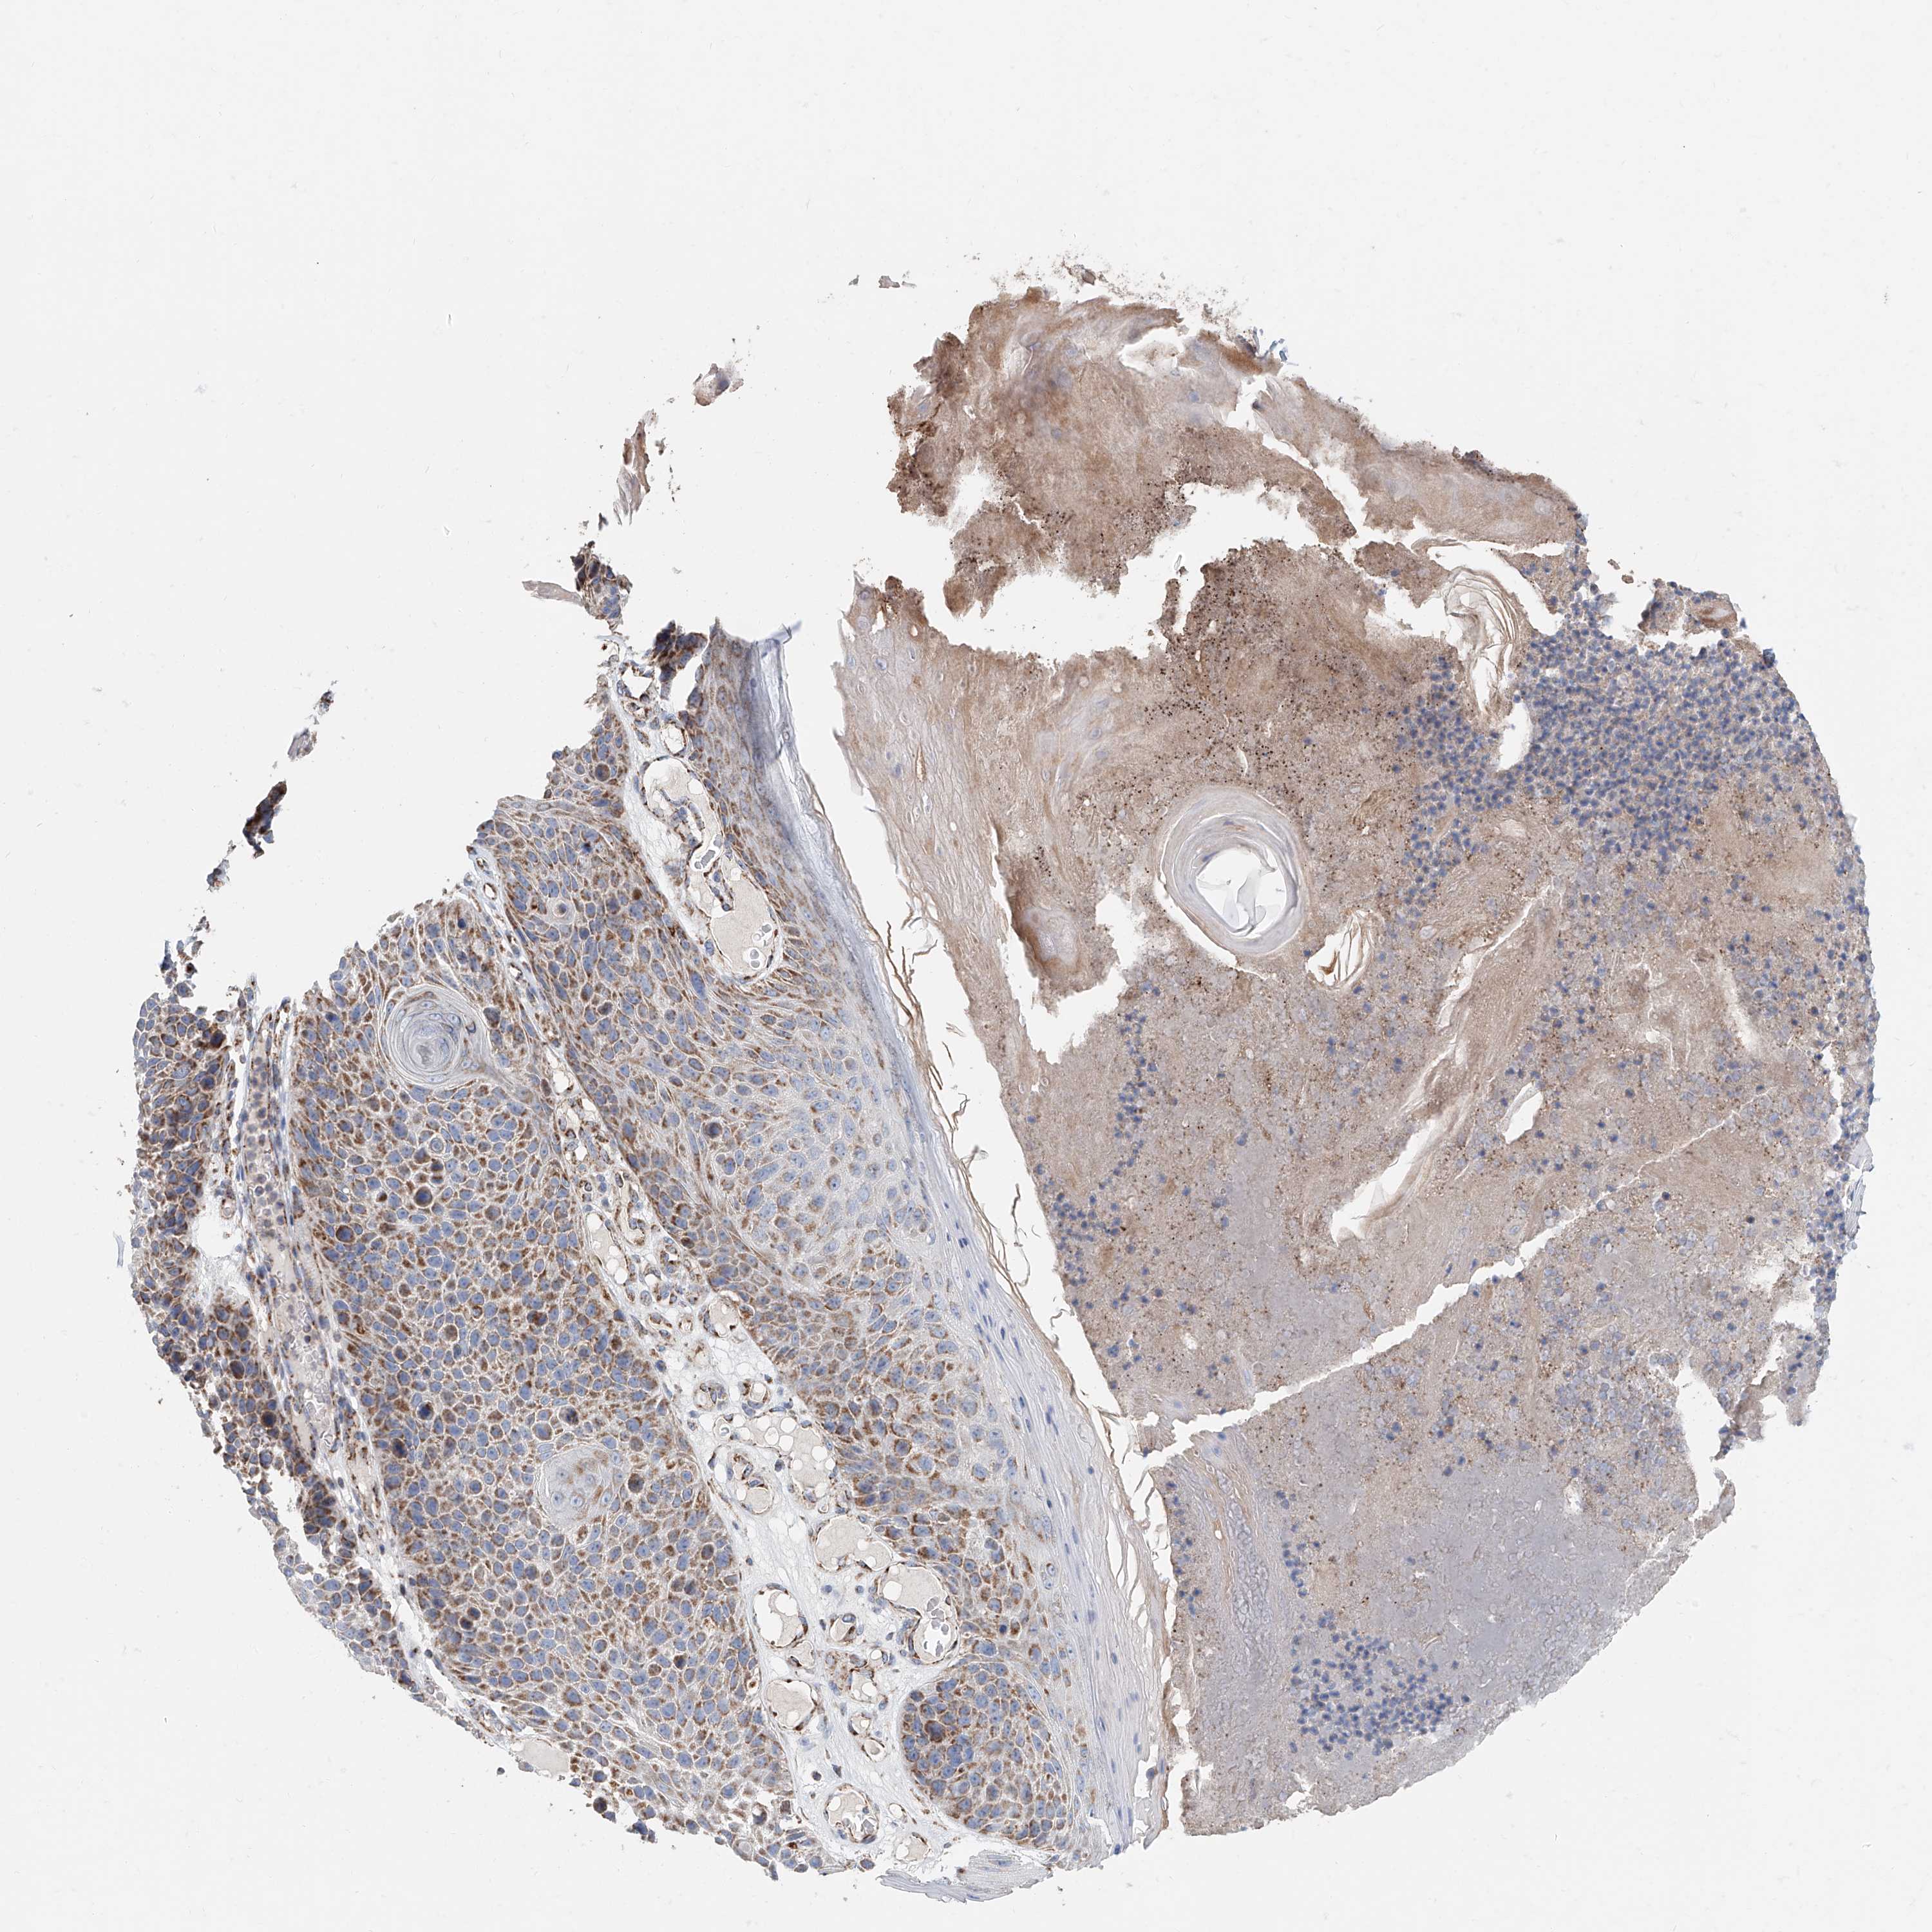

SKIN CANCER - Protein expressioni

A mouse-over function shows sample information and annotation data. Click on an image to view it in a full screen mode. Samples can be filtered based on level of antibody staining by selecting one or several of the following categories: high, medium, low and not detected. The assay and annotation is described here.

Antibody stainingi

Antibody staining in the annotated cell types in the current human tissue is reported as not detected, low, medium, or high, based on conventional immunohistochemistry profiling in selected tissues. This score is based on the combination of the staining intensity and fraction of stained cells.

Each image is clickable and will lead to virtual microscopy that enables deeper exploration of all samples and also displays staining intensity scores, fraction scores and subcellular localization as well as patient and tissue information for each sample.

Antibody HPA008455

Antibody HPA031125

Antibody CAB002781

Antibody CAB068195

Staining

High

Medium

Low

Not detected

Intensity

Strong

Moderate

Weak

Negative

Quantity

>75%

75%-25%

<25%

None

Location

Nuclear

Cytoplasmic/membranous

Cytoplasmic/membranous,nuclear

Squamous cell carcinoma, NOS

Squamous cell carcinoma, metastatic, NOS

Basal cell carcinoma

Papilloma, NOS